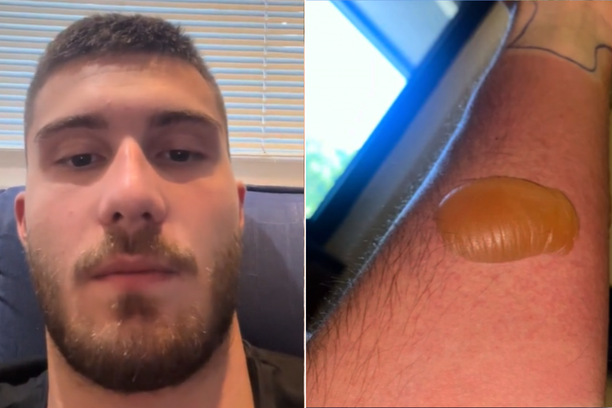

Influencer Marko Kovačević podijelio je na TikToku svoje dramatično iskustvo nakon što je doživio ozbiljan ugriz koji ga je odveo u bolnicu na nekoliko dana. Priča počinje jedne večeri na splavi na Savi, gdje je Marko bio u društvu prijatelja. Sljedeće jutro probudio se s velikim žutim plikom na ruci, za koji je prvo mislio da je opeklina od cigarete. Međutim, prijateljica mu je savjetovala da se posavjetuje s liječnikom.

Brzo nakon toga, njegovo stanje se pogoršalo, a na hitnoj službi su otkrili da je riječ o ugrizu pauka. Unatoč injekcijama, Markovo stanje nije se poboljšalo, već je ruka izgledala još gore nego prije. ‘Nakon tri sata čekanja, liječnica mi je rekla da moram ostati na hitnom liječenju u bolnici. Kada sam je upitao zašto, rekla mi je da ne može objasniti i da sumnjaju na najgore’, ispričao je Marko u svom TikTok videu.

Poslali su ga na analizu krvi te je dva dana čekao rezultate. ‘U glavi su mi bili najgori scenariji, ovo mi se na ruci krenulo povećavati i širiti, a ja ne znam što se događa’, ispričao je Marko.

Na sreću, najgori scenarij nije se ostvario. Naime, liječnici su mislili da je insekt iz Dominikanske Republike i Afrike ugrizao Marka, čiji otrov polako razgrađuje mišiće. U najgorem slučaju, jedini način liječenja bio bi amputacija dijela ruke kako bi se spriječilo širenje otrova, prenosi Večernji list

Ipak, Marko je 20 dana proveo u bolnici gdje mu je oteklina postala još veća. Pregledalo ga je preko 20 liječnika i nitko nema objašnjenje za njegovu reakciju na ovaj ugriz, niti za identitet insekta koji je uzrokovao problem. ‘Ne postoji medicinsko objašnjenje za ovo što se meni dogodilo’, dodaje Marko.

Ipak, Marko je 20 dana proveo u bolnici gdje mu je oteklina postala još veća. Pregledalo ga je preko 20 liječnika i nitko nema objašnjenje za njegovu reakciju na ovaj ugriz, niti za identitet insekta koji je uzrokovao problem. ‘Ne postoji medicinsko objašnjenje za ovo što se meni dogodilo’, dodaje Marko.